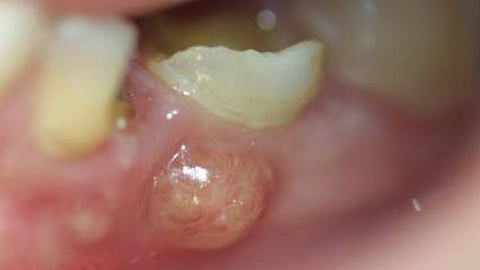

A dental abscess is a pocket of pus that forms at the root of a tooth or in the gums due to an infection. The infection usually starts from tooth decay, gum disease, or a crack in the tooth. It's important to seek treatment quickly to avoid serious complications.

The most common symptom of a dental abscess is severe tooth pain, which may come on suddenly. You may also notice swelling in your gums, face, or jaw. Other signs include a bad taste in your mouth or difficulty swallowing.

Some people experience fever or a general feeling of being unwell. A dental abscess can also cause sensitivity to hot or cold food and drinks. The symptoms can worsen if the infection spreads, so don't wait too long to see a dentist.

Treatment for a dental abscess usually starts with draining the infection. A dentist may also prescribe antibiotics to help clear up the infection. In some cases, a root canal may be necessary to save the affected tooth.